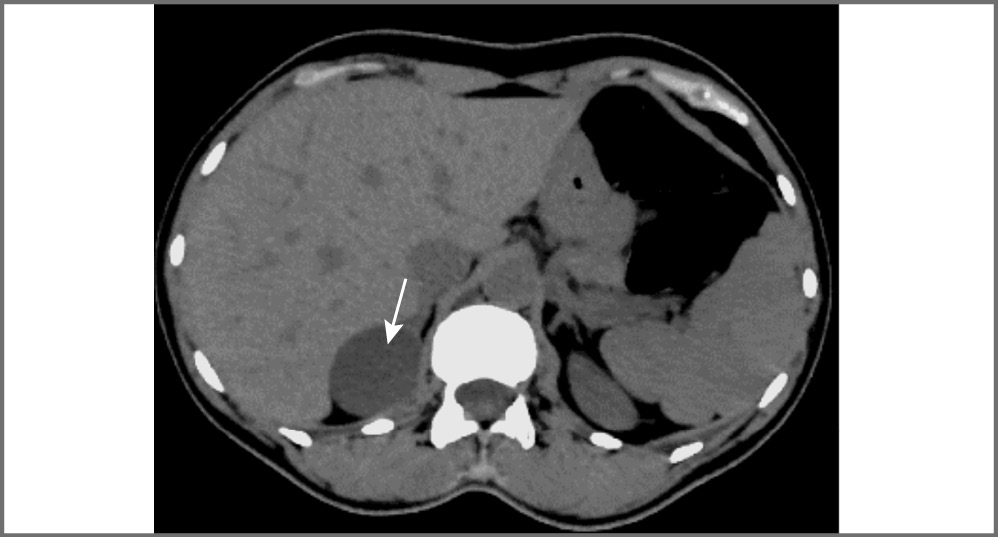

Феохромоцитома – опухоль, происходящая из хромаффинных клеток мозгового вещества надпочечников, и примерно в 90% случаев она секретирует катехоламины, что сопровождается повышенным уровнем метанефринов (метаболитов катехоламинов) в сыворотке крови и моче. Феохромоцитомы вненадпочечниковой локализации называются параганглиомами. КТ-картина феохромоцитом имеет разные признаки. Размер может варьировать от 1,2 до 15 см, в среднем около 5 см. Небольшие образования чаще однородны, в то время как более крупные обычно неоднородны с участками жидкостной плотности (зонами некроза), зонами кровоизлияний, внутренними перегородками, а также обызвествлениями. Большинство опухолей интенсивно накапливает контрастный препарат в артериальную фазу с последующим умеренным его вымыванием к отсроченной фазе. Контуры образования, как правило, четкие, ровные за счет наличия капсулы (рис. 3). В редких случаях феохромоцитомы могут в структуре иметь включения макроструктурного жира, что также характерно и для миелолипом [14].

Рис. 3. Феохромоцитома правого надпочечника (стрелка). МСКТ, аксиальная проекция: a – нативная фаза; b – артериальная фаза; c – венозная фаза; d – отсроченная фаза.

Следует отметить, что, несмотря на то, что выраженное вымывание контрастного препарата для феохромоцитом нехарактерно, в редких случаях они могут иметь характеристики вымывания, аналогичные аденомам (APW более 60% и RPW более 40%), что затрудняет установку диагноза [14, 15].